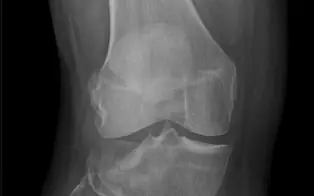

Genou

Entorse de genou

Fracture de patella

Luxation de genou